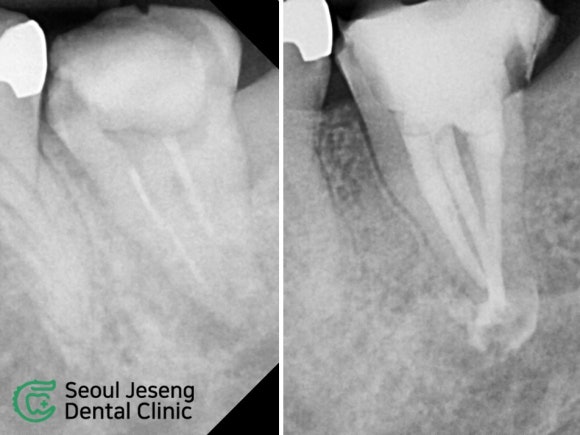

[치료사례] 재신경치료 (3)

#재신경치료 #미세현미경신경치료 #자연치아살리기 #치과보존과전문의 #신촌치과 #신촌서울재생치과